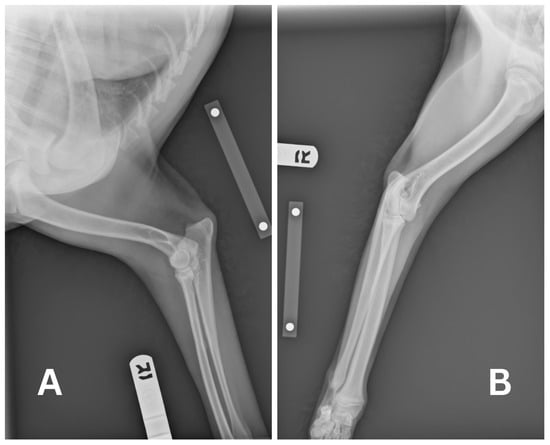

At the time of presentation to the emergency department, the patient had no clinical signs. Physical examination was unremarkable other than her missing 404 tooth with stitches in place and a shaved right cephalic region from the prior PIVC site. Remnants of the PIVC were compared to an actual 20-gauge PIVC. The estimated missing catheter tip was 18–22 mm long. At this point, a full-body CT scan was recommended, for which the patient was anesthetized on the same day. The patient was premedicated with 0.004 mg/kg of fentanyl (50 mcg/mL, Fentanyl Citrate, Hospira, Lake Forest, IL, USA) IV, and then induced with 0.2 mg/kg of midazolam (5 mg/mL, Midazolam Injection, Avet Pharmaceuticals, East Brunswick, NJ, USA) IV and propofol to with a total volume of 6 mL IV. Anesthesia was maintained with isoflurane in 100% oxygen. The patient was placed in sternal recumbency for the CT scan (Somatom Emotion 16, Siemens Healthineers, Malvern, PA, USA). Protocol parameters were as follows: kVp: 130; exposure time: 600; and slice thickness: 0.75 mm. Initially, the full-body CT scan was unremarkable, with no linear hyperattenuating structure visualized in the cephalic vasculature, pulmonary vasculature, or cardiac silhouette. The skull, cervical region, thorax, abdomen, pelvis, and pelvic limbs were reported as normal, and no remnant of the PIVC could initially be identified. No complications occurred during anesthesia and recovery post-operatively was uneventful. The patient was discharged the same day. Since the PIVC had to be present in the patient, a misdiagnosis was suspected. The authors requested a second opinion from another board-certified radiologist, and the CT report was amended as a small linear hyperattenuating structure was visualized in the ventral aspect of the left caudal lung lobe, as seen in Figure 2. It was assumed that this was the PIVC tip due to the difference in Hounsfield Units (HU) between the linear structure of the PIVC (60 to 100 HU) compared to the surrounding blood vessels (30 to 60 HU) and lung parenchyma. The surrounding pulmonary parenchyma was normal with no pulmonary thromboembolism.

Figure 2. CT scan displaying hyperattenuating linear structure in the left ventral lung lobe, suspected at the time to be the migrated intravenous catheter estimated to be 20 mm in length. Sagittal (A), axial (B), and coronal (C) views are displayed with visualization of the suspected structure in each view indicated by the red circle.

Due to these findings, the patient was readmitted the next day for a left lateral thoracotomy with potential lung lobectomy. A repeat CT scan was recommended to verify the location of the PIVC tip immediately prior to surgery. A complete blood count (CBC) and non-steroidal anti-inflammatory drug (NSAID) panel, consisting of alkaline phosphatase, alanine aminotransferase, aspartate aminotransferase, blood urea nitrogen, and creatinine performed prior to repeat CT imaging, showed no abnormalities except eosinopenia (0.00 K/uL; reference range: 0.06–1.23 K/uL). The initial partial thromboplastin time (PTT) result (>300.0 s with a reference range of 72–102 s) was considered erroneous; repeat testing confirmed a value within the reference range of 93.0 s. The patient underwent general anesthesia and was premedicated with 1 mg/kg of maropitant and 0.19 mg/kg of hydromorphone (10 mg/mL, Hydromorphone Hydrochloride, Pfizer, New York, NY, USA) IV. She was then induced with 0.2 mg/kg of midazolam IV and propofol to affect with a total of 6 mL IV (3.2 mg/kg total). She was maintained on isoflurane in 100% oxygen with IV crystalloid fluids at 5 mL/kg/h. CT verified that the linear hyperattenuating structure remained in the peripheral pulmonary artery within the ventral aspect of the left caudal lung lobe.